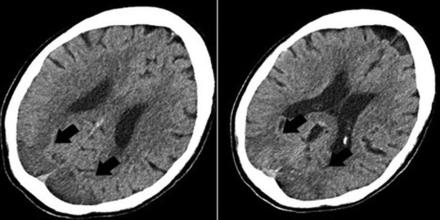

He subsequently developed fever and cough on March 17, had polymerase chain reaction testing positive for SARS-CoV-2, and was admitted into a local hospital for medical care. Two days later, the fever progressed to 105°F and he developed difficulty breathing and was transferred to a tertiary medical center for intensive care unit care and was placed on mechanical ventilation. On March 25, he developed shock with widely varying blood pressures from 70/30 to 180/90 mm Hg during his intensive care stay. On April 4, he was diagnosed with inflammatory cytokine release syndrome (high D-dimer, lactate dehydrogenase, C-reactive protein, and ferritin values) and developed an altered mental status. Noncontrast CT of the head was obtained and demonstrated focal vasogenic/cytotoxic edema in the posterior parieto-occipital regions bilaterally, which was subcortical in distribution, with a small right-sided hemorrhage (Fig 1); concurrently obtained CT venogram findings were normal. The patient was extubated and transferred to a medical floor on April 10, with gradual improvement in his mental status. MR imaging of the brain was performed on April 13 and confirmed vasogenic edema in the posterior parieto-occipital regions with subacute blood products suggestive of hemorrhagic posterior reversible encephalopathy syndrome (PRES). SWI revealed extensive petechial hemorrhages diffusely distributed throughout the corpus callosum (Fig 2).

Axial noncontrast CT demonstrates edema in the posterior parieto-occipital regions (black arrows) with a superimposed small right-side hemorrhage (white arrow).